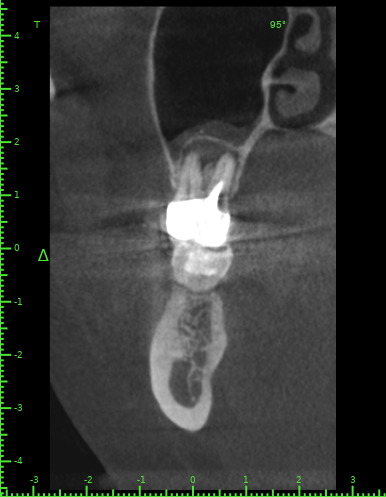

Katya88 Опубликовано 28 июля, 2021 Поделиться Опубликовано 28 июля, 2021 Мой стоматолог терапевт советует удалить, так как там кисты, а ортопед советует найти того, кто займется лечением. КТ прилагаю https://drive.google.com/file/d/1Z-neEH63BszTXxa8bAOG1tgsrIrsqrVK/view?usp=drive_web Ссылка на комментарий

Женька Опубликовано 28 июля, 2021 Поделиться Опубликовано 28 июля, 2021 2.6 2.7 3.7 На 3.5 и 1.5 стоит обратить внимание 1.5 1 Ссылка на комментарий

Женька Опубликовано 28 июля, 2021 Поделиться Опубликовано 28 июля, 2021 54 минуты назад, Katya88 сказал: 1.5 менять коронку как минимум снять существующую конструкцию и посмотреть клинически на зуб(ы). 1.5 на КТ выглядит удручающе. По остальным, я бы поддержал ортопеда и попытался зубы сохранить. Пусть коллеги меня поправят. 1 1 Ссылка на комментарий